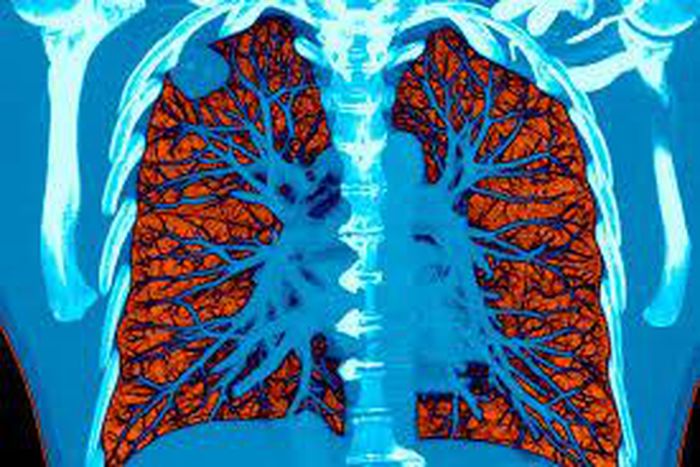

AI took a test to detect lung cancer, it got an A

Computers were as good or better than doctors at detecting tiny lung cancers on CT scans, in a study by researchers from Google and several medical centers.

In the new study, the researchers applied artificial intelligence to CT scans used to screen people for lung cancer, which caused 160,000 deaths in the United States last year and 1.7 million worldwide. The scans are recommended for people at high risk because of a long history of smoking.

Tested against 6,716 cases with known diagnoses, the system was 94% accurate. Pitted against six expert radiologists, when no prior scan was available, the deep learning model beat the doctors: It had fewer false positives and false negatives. When an earlier scan was available, the system and the doctors were neck and neck.